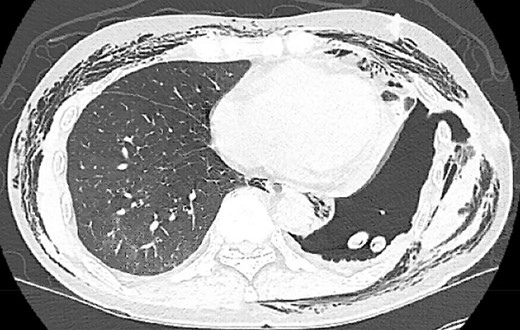

A 68-year-old male, current smoker with chronic cough and night sweats was diagnosed with a suspicious 13 mm spiculated left lower lobe nodule (Fig. 1). His medical history included a 35+ pack-year smoking history, treated tuberculosis, hypertension, peripheral vascular disease, aortic atherosclerosis and asthma with severe chronic obstructive pulmonary disease (COPD) managed on low-dose steroid taper. Pulmonary function testing and positron-emission tomography (PET) demonstrated a forced expiratory volume (FEV1) of 40% with mildly PET-avid disease. The patient underwent VATS left lower lobe wedge resection of the left lower lobe nodule with mediastinal lymph node sampling. Extensive anthracosis and adhesive disease was seen. Pathology revealed benign parenchyma with fibrinous changes and organizing pneumonia.